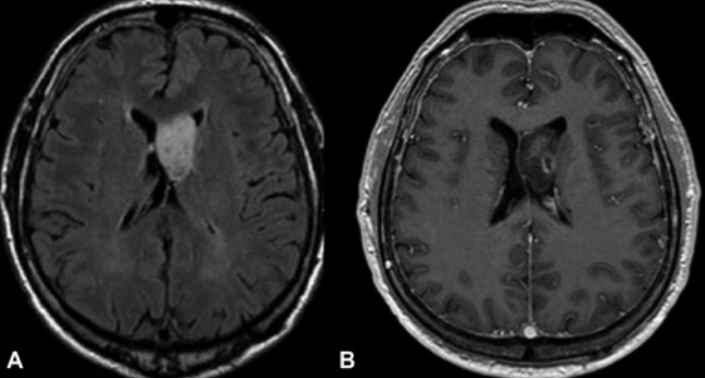

脑室肿瘤的诊断

影像学检查是脑室肿瘤诊断的关键。目前,磁共振成像(MRI)是较合适的成像方式。计算机断层扫描(CT)也被使用,特别是用于评估脑积水。在这两项研究中,都会通过静脉注射一种能提供图像对比度的药物,以便神经外科医生能在背景中看到肿瘤与正常大脑的对比。在某些情况下,神经外科医生可能使用无框架立体定向指导的MRI扫描。在这项研究中,在患者的头皮上放置不同标记(称为基准)后进行对比MRI。这些基准数据由计算机处理,计算机计算出肿瘤的位置并创建一个三维重建。这幅图像在手术时被用来帮助精确定位肿瘤,较大限度地切除肿瘤,减少对周围大脑的损伤。